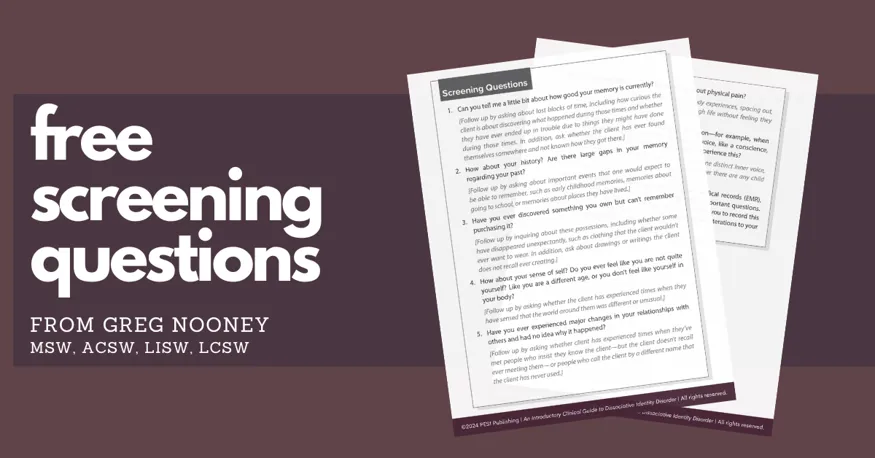

Use these free screening questions to help you get started in assessing Dissociative Identity Disorder, so you and your client can have early discussions that are instructive to the diagnostic process.

Use these free screening questions to help you get started in assessing Dissociative Identity Disorder, so you and your client can have early discussions that are instructive to the diagnostic process.